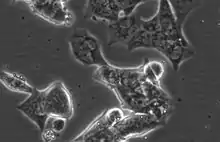

LAPC4 are a lowly adherent, epithelial cell line with high Androgen receptor and Prostate specific antigen expression.[4] Unlike the other commonly utilized, Androgen receptor positive prostate cancer cell lines LNCaP and VCaP, LAPC4 have high expression of Keratin 5, a basal marker, as well as the luminal markers Keratin 8 and Keratin 18.[4] LAPC4 also expresses mutated P53 (R175H). [4]

The cells have an approximate doubling time of 72 hours under typical culture conditions.[5]